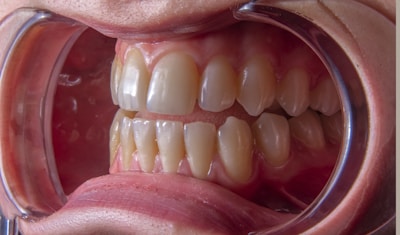

Orthodontie

Alignement des dents et des mâchoires pour un sourire harmonieux et fonctionnel.

Traitements modernes, confortables et adaptés à chaque âge.